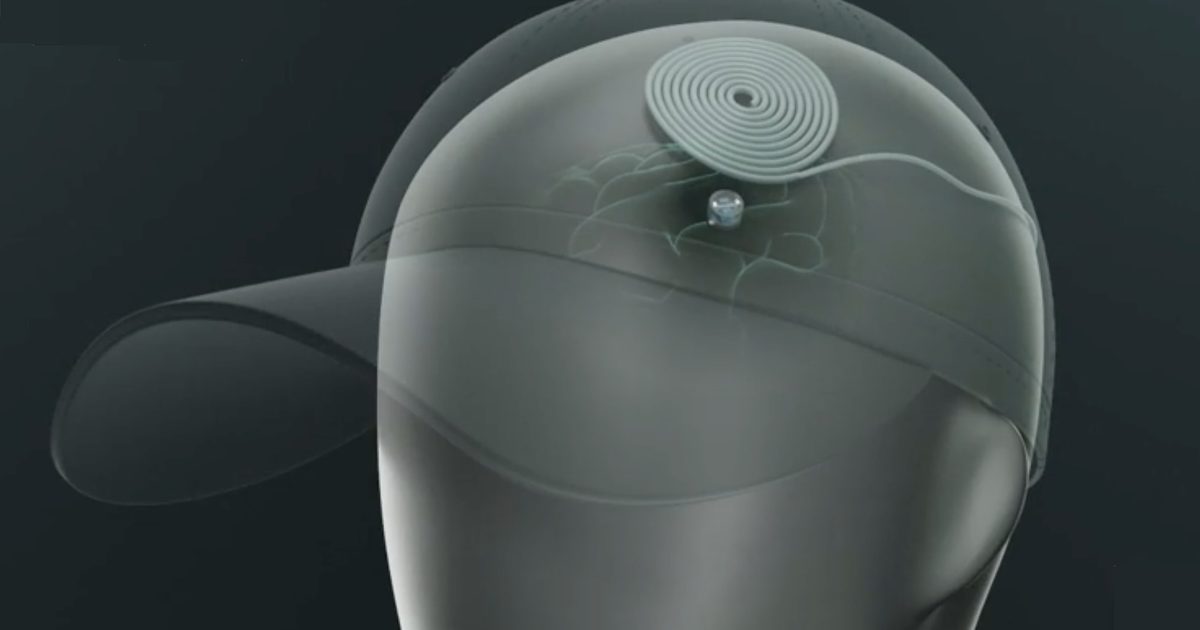

Ce minuscule implant cérébral pourrait traiter la dépression à la maison

Près de 3 millions d'Américains souffrent de dépression résistante aux traitements, ce qui signifie que les antidépresseurs ne fonctionnent tout…

Près de 3 millions d'Américains souffrent de dépression résistante aux traitements, ce qui signifie que les antidépresseurs ne fonctionnent tout…

Près de 3 millions d'Américains souffrent de dépression résistante aux traitements, ce qui signifie que les antidépresseurs ne fonctionnent tout…